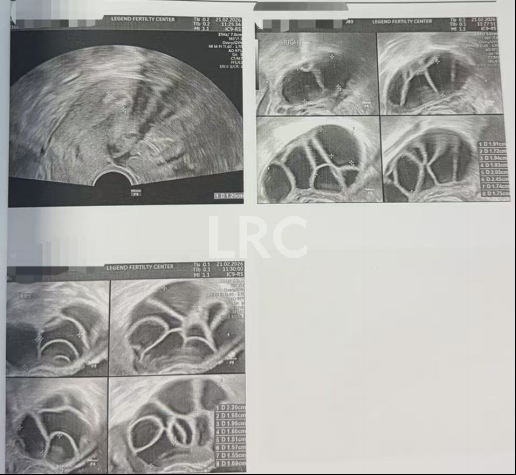

治疗结果

取卵及受精

取卵:15颗

成熟MII:10颗

ICSI受精:10颗

养囊成功:10颗

▲ C女士的养囊报告